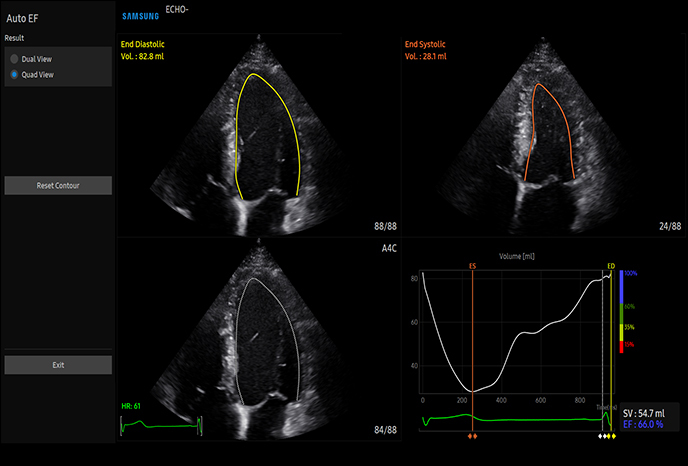

하이앤드 초음파 장비를

활용한 정밀 심장 검사

심장 질환 진단에서 가장 중요한 것은 ‘심장의 상태를 얼마나 정확하게 볼 수 있느냐’입니다. 저희 센터는 대학병원급 하이앤드 초음파 장비를 도입하여, 실시간 3D 렌더링으로 정밀 진단이 가능하며, 심장의 구조·혈류·기능을 실시간 고해상도로 관찰합니다.

미세한 판막 움직임, 혈류 속도 변화, 심방·심실 크기와 수축력까지 정밀하게 분석할 수 있어, 심장질환의 조기 발견과 치료 계획 수립에 큰 차이를 만듭니다.